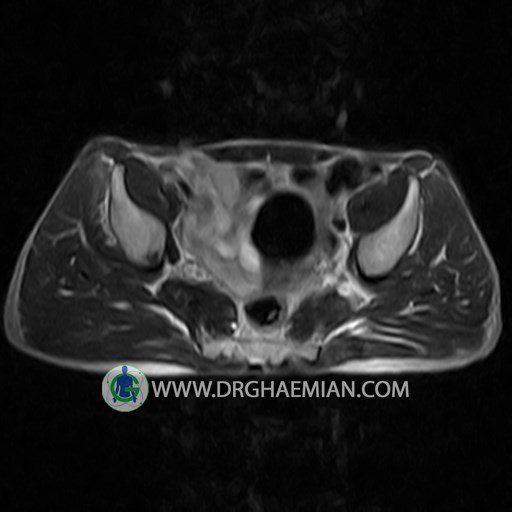

پزشکان اغلب از تصویربرداری ام آر آی برای تشخیص و درمان عارضه های پزشکی که فقط با استفاده از اشعه ایکس یا میدان مغناطیسی و امواج رادیویی قابل مشاهده است، استفاده می کنند. دستگاه ام آر آی تصاویر دقیق از ساختار های داخلی بدن ایجاد می کند. در این کیس استئومیلیت لگن، آتروز و سنیویت دیده می شود.

HIP JOINT MRI

( without contrast )

Technique : coronal STIR , coronal T2 , Axial T1 , axial T2 .

Each femoral shaft has normal margins and contains a normal bone marrow signal .

The imaged muscles and the lesser pelvis show no abnormalities .

– Heterogeneous signal change (high T2/STIR , low T1) in proximal metaepiphysis of left femur without articular surface irregularity suggestive for bone bruise (stress fracture?), osteomyelitis & arthritis and marrow infiltration (less probable)

– Left hip joint effusion suggestive for synovitis

are seen.

COMMENT: Clinical correlation and MRI with contrast are recommended.